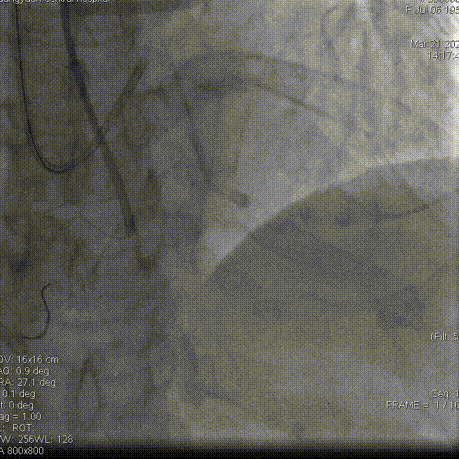

冠脉造影

左冠造影:左冠状动脉主干未见明显狭窄,前降支近中段慢性闭塞;回旋支近中段狭窄90%。

右冠造影:右冠状动脉近中段可见斑块,后降支近段狭窄60%。右冠远端可见向前降支中远段侧枝供血。

双侧造影:前降支近中段闭塞段清晰可见。